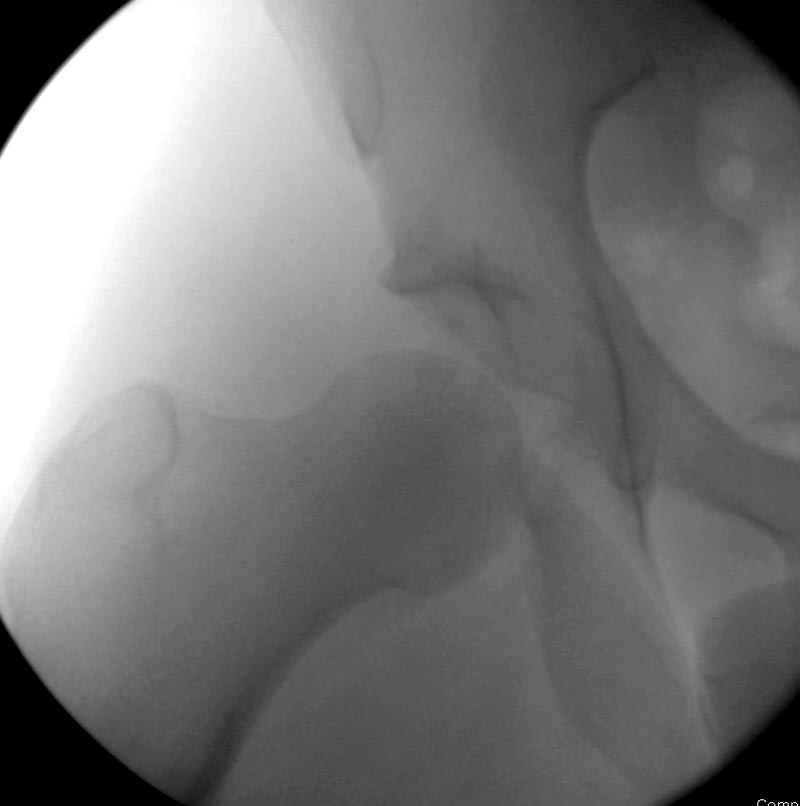

5:24 Рентгенограмма таза, вызывают врача ортопеда (снимок N1), его диагноз: закрытый переломо-вывих правого тазабедренного сустава, получает добро на закрытую репозицию в приемном отделении

N 2